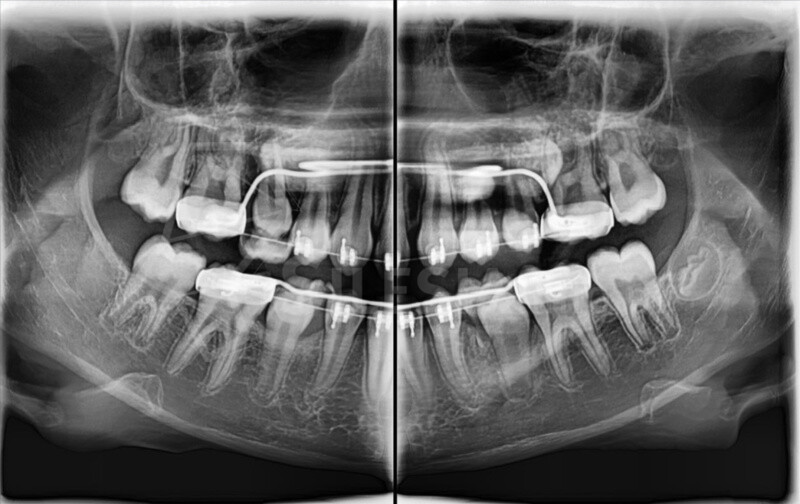

Zdjęcie panoramiczne (pantomogram) obejmuje całe uzębienie i szczęki, pokazując zmiany, których nie widać na zdjęciach punktowych RTG – takie jak torbiele, guzy, stany zapalne czy zwyrodnienia stawów.

CBCT (tomografia stożkowa) to nowoczesne badanie 3D, które pokazuje zęby, kości, zatoki i stawy skroniowo-żuchwowe w pełnym trójwymiarze. Umożliwia bardzo dokładne zaplanowanie leczenia chirurgicznego, ortodontycznego, implantologicznego i laryngologicznego.